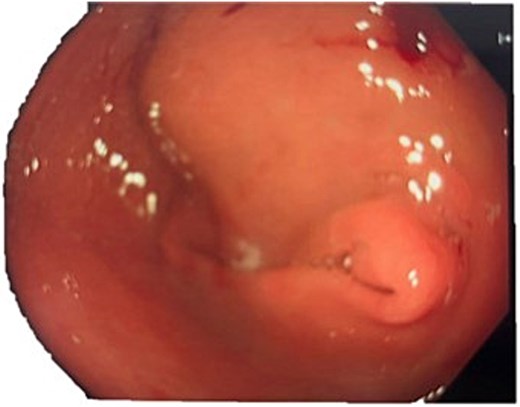

A computed tomography (CT) of the abdomen with IV portal venous contrast demonstrated proximal gastric dilatation due to a 7.6 cm gastric pyloric mass concerning for malignancy (Fig. 1). Other findings included small volume pancreatic parenchymal calcifications with no ductal dilatation. She was decompressed via nasogastric tube and planned for gastroscopy and feeding tube insertion. Gastroscopy demonstrated a partially obstructing extraluminal mass at the gastric antrum, able to be traversed to the second part of the duodenum (Fig. 2). A nasojejunal feeding tube was placed and the nasogastric tube was left in for decompression. An endoscopic ultrasound the following day demonstrated Doppler signal in the mass, confirmed to be a large 6.2 × 4.2 × 7.0 cm pseudoaneurysm arising from the GDA on a subsequent CT mesenteric angiogram (Fig. 3). Coil angioembolization of the pseudoaneurysm was successfully done via common femoral access (Fig. 4). She was commenced on NJ feeding and supplemental parenteral nutrition. She recovered well and was discharged on puree diet. Repeat imaging at 4 weeks demonstrated resolution of the pseudoaneurysm and returned to normal diet 6 weeks post presentation.

Endoscopic photograph showing large partially obstructing extraluminal mass at the gastric antrum.